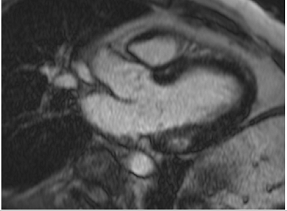

The cardiovascular magnetic resonance protocol used for assessment of hypertensive patients. The described protocol can be acquired within 45–50 min. Images are examples from patients with hypertensive heart disease.

Similar to echocardiography, LV geometry can be assessed using relative wall thickness (RWT) and CMR-specific normal values for LV myocardial mass (Figure 2). LA dimensions can be assessed with Simpson’s biplane or area-length methods from the standard views, or more precisely with a volumetric assessment using an atrial short-axis stack. LA enlargement is a reliable marker of diastolic dysfunction (chronically elevated LV filling pressures) in the absence of mitral valve disease [31]. The recently introduced left atrial coupling index (LACI) is a ratio of the indexed left atrial end-diastolic volume (LAVI) in relation to the left ventricular end-diastolic volume (LVEDVI) [32]. This ratio may offer prognostic information regarding cardiovascular events such as atrial fibrillation, heart failure, and coronary artery disease-related death.

Figure 2.

Tissue characterization with Late Gadolinium Enhancement (LGE) and Extracellular Volume (ECV) Map. Adapted with permission from [33].